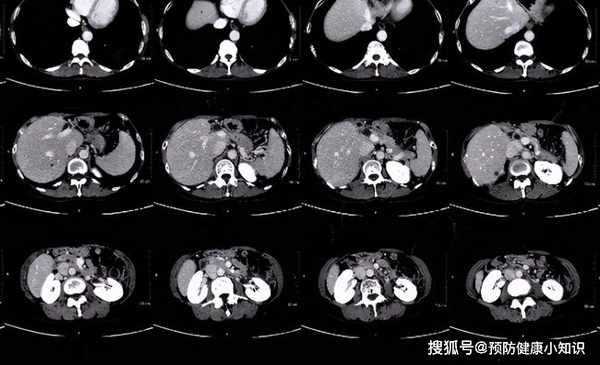

在一個休息日,米娜預約了體檢,醫生接診米娜後,發現米娜雖然妝容精緻,卻還是難掩面色發黃且黑眼圈的情况,建議其做一個肝CT。

結果顯示肝臟內部有明顯占位,22歲的米娜被確診為肝癌。